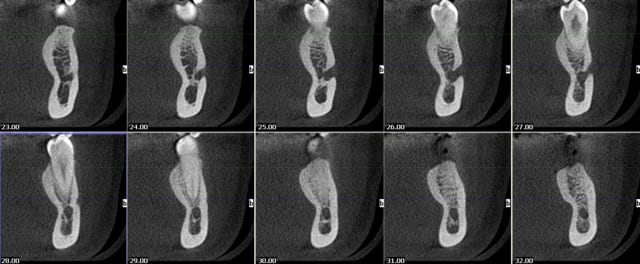

Bon finalement j'ai fait mon choix, cone beam installé hier !

Vatech Ewoo.

Pour moi les plus :

- taille de champ variable: 5*5 8*5 8*8 12.5*8

- vraie combo pano/cone beam

- interface sympa

- artefact métallique limité

- Logiciel d'imagerie et planification implantaire très bien

(pour info c'est une version d'Ondemand3D à l'essaie pour 90j ici:

http://www.ondemand3d.com/Content/Download/Trial.aspx prix du soft environ 5000$)

- budget compétitif

quelques clichés d'essais